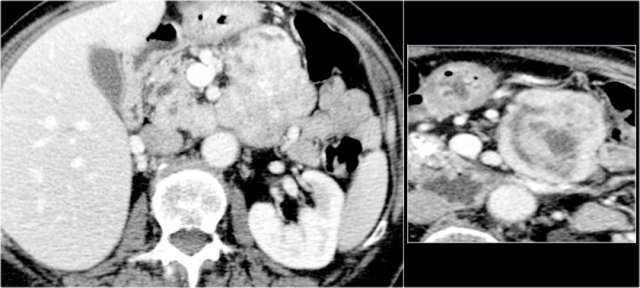

CT-images of an IPMN with a dilated pancreatic duct (blue arrows).

Notice enhancing solid nodule in the pancreatic head (red arrow).

Continue with the ultrasound-image.

The US-image shows a large branch-duct component within the pancreatic head.